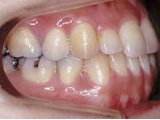

症例2:乱杭歯「歯並びが乱れている」

治療前 治療後